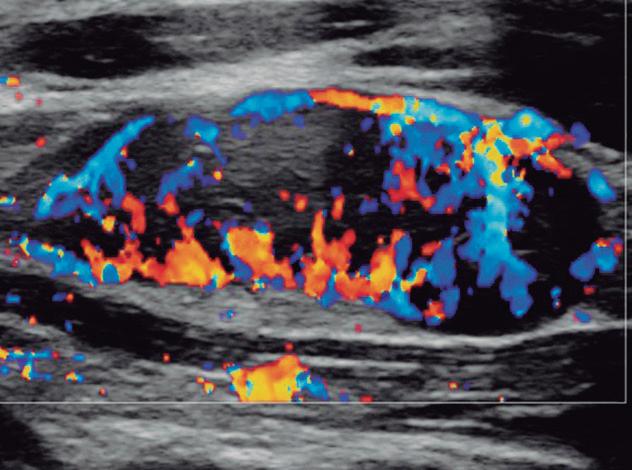

Fig. 2-31. Doppler tipo “roda de carroça” da hiperplasia nodular focal.